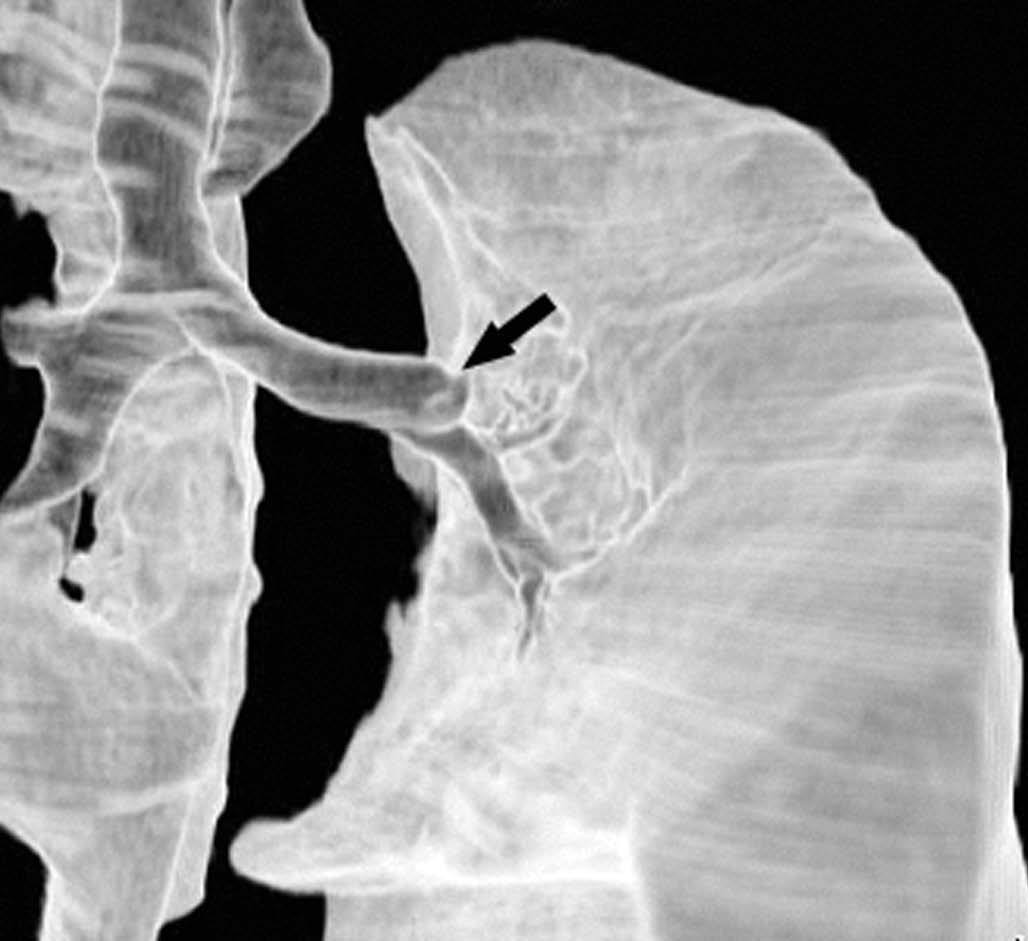

Pese a las conocidas limitaciones de la TC, ésta continúa siendo la técnica de elección en la estadificación del tumor en los pacientes con CPNM; su sensibilidad y especificidad en la determinación de la infiltración de pared oscilan entre el 38 y el 87% y del 40 al 90%, respectivamente, según las series. El desarrollo de nuevos equipos de TC helicoidal y principalmente las TC multidetectoras (TCMD) proporcionan unas imágenes 2D de mayor resolución con la posibilidad de hacer reconstrucciones multiplanares (MPR) en distintos planos del espacio e incluso 3D con la consiguiente mejora de la valoración del tumor, su extensión e infiltración de estructuras vecinas5 (fig. 4). Así, con la TCMD se puede poner de manifiesto con mayor fiabilidad la invasión de la cisura, la pared torácica o el mediastino, y además es capaz de determinar, gracias a las reconstrucciones de volumen, la relación exacta del tumor con la vía aérea (fig. 5). El progreso en la capacidad diagnóstica deriva del incremento en la resolución de las imágenes obtenidas y de la posibilidad de emplear nuevas aplicaciones como la broncoscopia virtual y la visualización en tiempo real. La broncoscopia virtual es útil para valorar la invasión del árbol traqueobronquial con la finalidad de planificar la cirugía, también como guía para el fibrobroncoscopista y, por último, porque permite ver el árbol bronquial distal a la estenosis (fig. 6)6. La capacidad de ver la imagen en tiempo real es especialmente útil cuando se emplea como guía en maniobras intervencionistas como biopsias percutáneas, ya sea con finalidad diagnóstica o como parte de la estadificación (fig. 7). Esta técnica de guía de biopsia denominada TC fluoroscopia reduce el número de pases y el tiempo global de la exploración, implica un menor riesgo de lesión de estructuras y permite la visualización inmediata de las posibles complicaciones7.

Fig. 6.--Broncoscopia virtual. (A) Reconstrucción coronal que muestra una masa hiliar derecha (T) con infiltración del ángulo traqueobronquial. (B) Visión endoscópica del tumor en la que se observa la infiltración de la tráquea y la relación con la carina (asterisco).